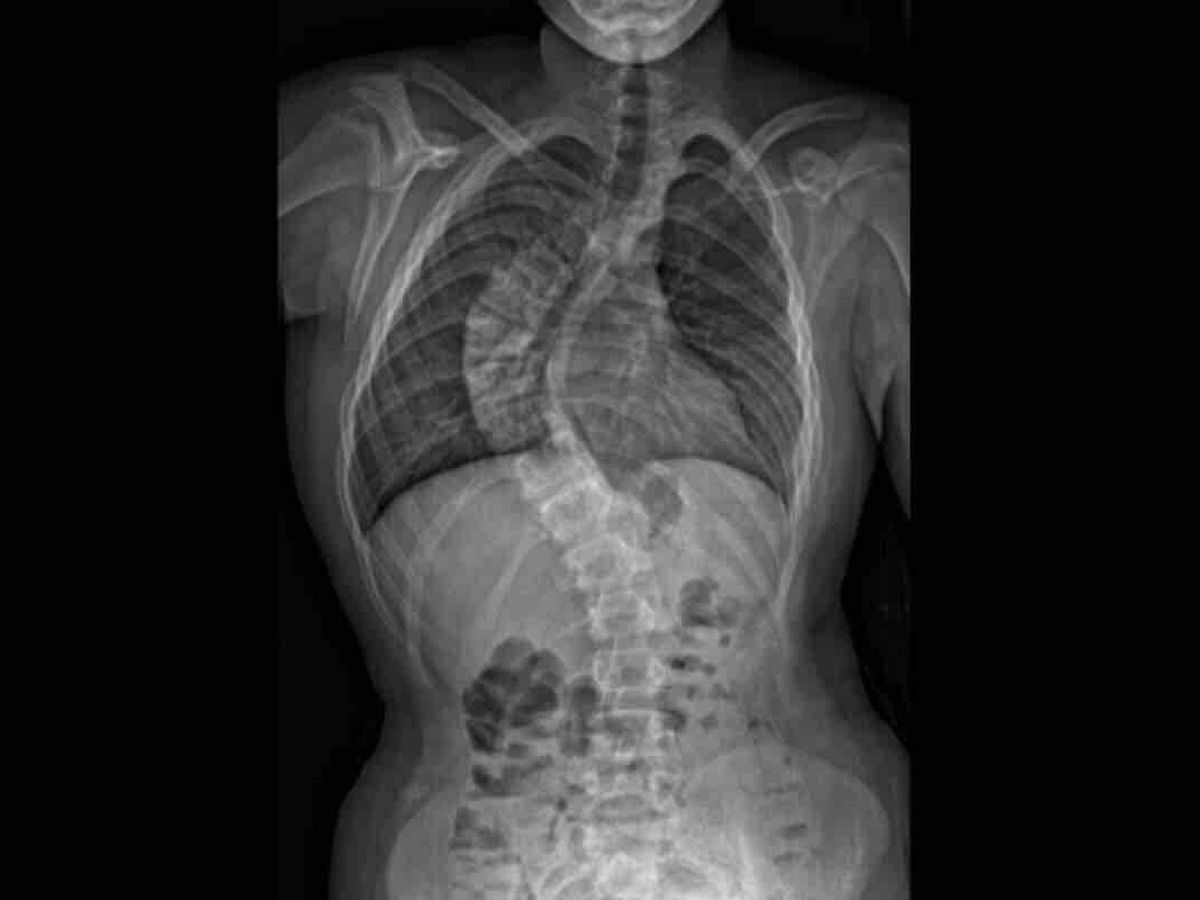

Our oldest son Jared was diagnosed with infantile idiopathic (no known cause) scoliosis at 14 months old.

His curve measured 14 degrees at that time and was considered mild, so the Doctor’s recommendation was to wait and watch it to see what it did.

Fast forward a few years.... Jared’s scoliosis continued to grow through the years until at age 4 the curve had reached 31 degrees. He started wearing a Milwaukee TLSO body brace that we were hopeful would hold his curve from progressing so we could avoid major surgery on his little body.

Unfortunately with recent growth spurts his curve has become “a runaway train”as quoted by his Doctor.

Jared is now at the point of requiring surgery to stop his curve from progressing to the point of crushing his lungs and heart, and causing chronic debilitating pain.

It was considered severe at 40 degrees and he is now at 71 degrees (maybe even more by now).